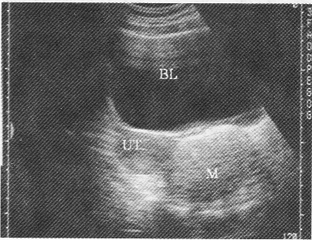

1.女性,28歲,停經27周,產前超聲檢查如圖,最可能的診斷為

A.胎兒畸形,腦積水

B.胎兒畸形,臍膨出

C.胎兒畸形,多囊腎

D.胎兒畸形,無腦兒

E.胎兒畸形,露腦畸形

正確答案:D解題思路:顱骨強回聲光環消失,眼球突出呈蛙樣面容且羊水過多。